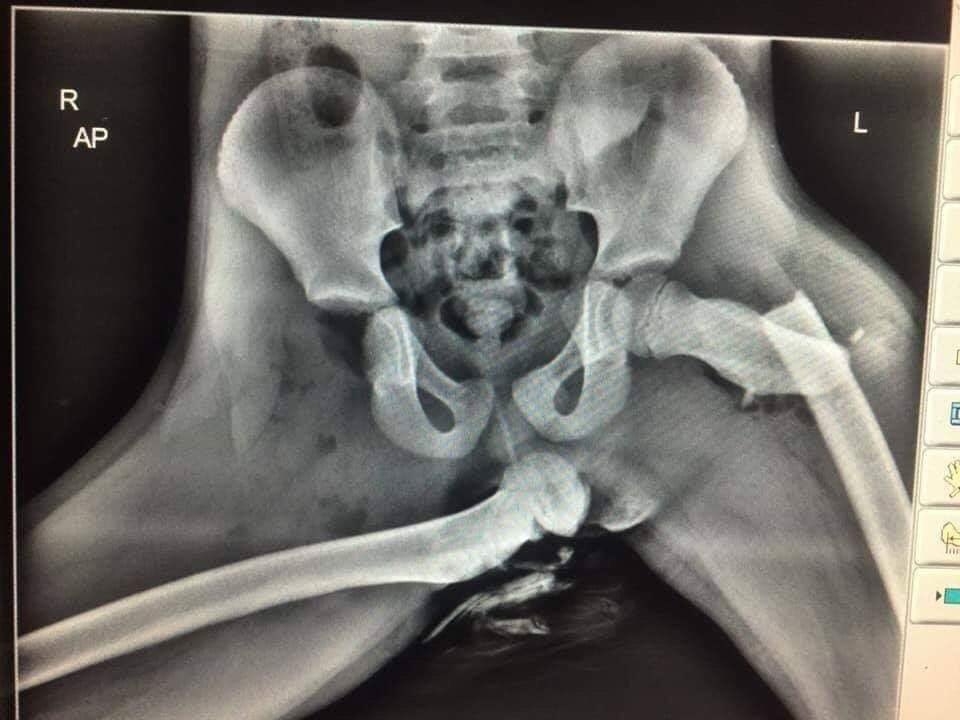

에어백 터지면서 골반탈골에 다리뼈 갈비뼈 척추뼈가 바스러지더군요 심지어 에어백에 밀린 무릅이 안면을 강타해서 자기무릅에 자기얼굴뼈가 아작나는 경우도